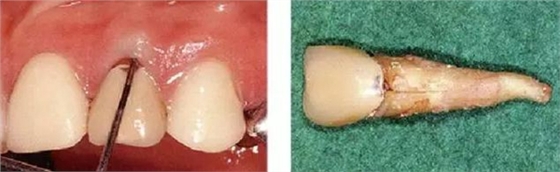

●埋伏齒矯正治療引起的附著喪失

15歲女性。對(duì)完全埋伏的右上尖牙進(jìn)行開(kāi)窗矯正使得牙齒崩出、整直。矯正結(jié)束后已出現(xiàn)7mm的牙周袋,并且有牙周出血現(xiàn)象,X片上也可觀察到骨吸收。推測(cè)是由于埋伏引起的偶發(fā)性附著喪失。有必要進(jìn)行徹底的控制,但在對(duì)患者進(jìn)行說(shuō)明后沒(méi)有獲得理解,中途放棄來(lái)院了。

主訴為其他部位而來(lái)院時(shí)拍攝的X片可觀察到,5年后和7年后的牙周袋雖然沒(méi)有大程度惡化,但依然有很深的牙周袋和出血現(xiàn)象。